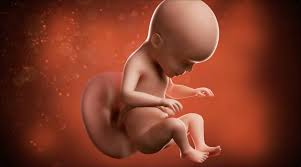

Pain in the abdomen and under the ribs can be caused by the growing uterus, which presses the internal organs. Your baby is now the size of a beetroot, measuring around 14 inсhes (35.6 cm) in length and weighing around 2 pounds (907 g). Baby is still working on putting on weight to get adorably chubby, and their eyes are looking around, though there's not enough pigment in the iris to determine eye color quite yet. 26 to 28 weeks (photos) every pregnant belly is different. Pregnancy checklist at 26 weeks.

The lungs are now starting to produce surfactant, which is a substance that helps the lungs inflate properly with each breath. Your baby still looks very lean, but he will gain fatty supplies and increase weight gradually throughout the remaining weeks of the pregnancy.   this week, baby weighs just about 32 ounces or 2 pounds (902 grams). Then see pregnancy bumps from 29 weeks to 31 weeks. Beef, veal, lamb and pork roasts, chops and steaks: In addition to a childbirth class, you may want to take classes on baby care, breastfeeding, and infant cpr. Pregnancy checklist at 26 weeks. Baby is still working on putting on weight to get adorably chubby, and their eyes are looking around, though there's not enough pigment in the iris to determine eye color quite yet.

Your age, previous pregnancies, height, build and fitness all affect the way your pregnant tummy looks. At 26 weeks, your baby's lungs are hard at work, getting ready to take those first breaths once he's born. Your baby still looks very lean, but he will gain fatty supplies and increase weight gradually throughout the remaining weeks of the pregnancy. What are the chances of baby surviving if is born at 26 weeks? 26 weeks pregnant with twins. Now's the perfect time to take one last trip before your baby's born. What is happening in 26th week of pregnancy pain sensations at 26 weeks pregnancy. In addition to a childbirth class, you may want to take classes on baby care, breastfeeding, and infant cpr. Dec 12, 2019 · 26 weeks pregnant: 26 to 28 weeks (photos) every pregnant belly is different. The baby's movements can cause you pain, as the baby starts feeling confined, lacks of free space for movements. How big is your baby at 26 weeks pregnant? Pain in the abdomen and under the ribs can be caused by the growing uterus, which presses the internal organs.

In addition to a childbirth class, you may want to take classes on baby care, breastfeeding, and infant cpr. Baby is still working on putting on weight to get adorably chubby, and their eyes are looking around, though there's not enough pigment in the iris to determine eye color quite yet. How big is your baby at 26 weeks pregnant? Dec 12, 2019 · 26 weeks pregnant: Your age, previous pregnancies, height, build and fitness all affect the way your pregnant tummy looks. Now's the perfect time to take one last trip before your baby's born. Pregnancy checklist at 26 weeks. At 26 weeks, your baby's lungs are hard at work, getting ready to take those first breaths once he's born. Your baby is now the size of a beetroot, measuring around 14 inсhes (35.6 cm) in length and weighing around 2 pounds (907 g). What my baby looks like at 26 weeks pregnant? What to expect from babies born at 26 weeks? Your baby still looks very lean, but he will gain fatty supplies and increase weight gradually throughout the remaining weeks of the pregnancy. Pain in the abdomen and under the ribs can be caused by the growing uterus, which presses the internal organs.